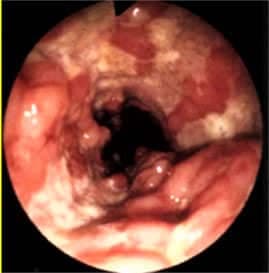

Enflamatuar Bağırsak Hastalığı Nedir?

Enflamatuar (İnflamatuar) Bağırsak Hastalığı Nedir? Bağırsakların kronik olarak herhangi bir bulaşıcı mikrop olmadan iltihaplanmasına neden olan bir...